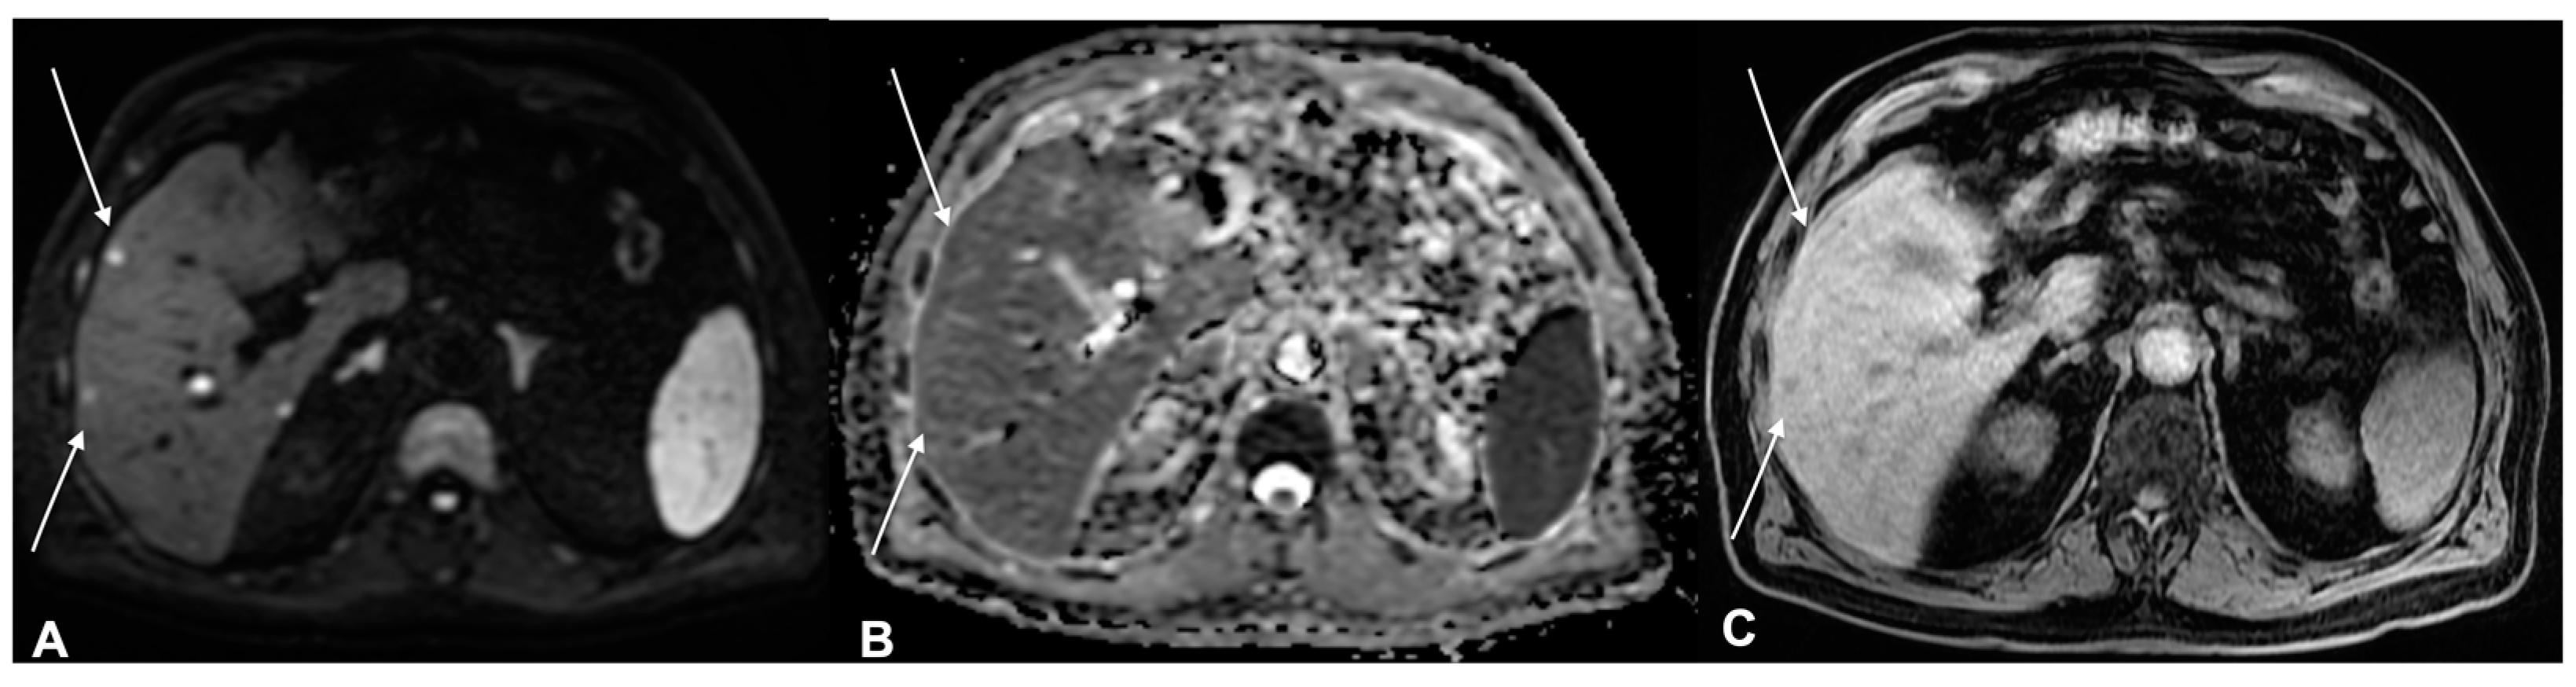

- Granata, V.; Fusco, R.; Filice, S.; Catalano, O.; Piccirillo, M.; Palaia, R.; Izzo, F.; Petrillo, A. The current role and future prospectives of functional parameters by diffusion weighted imaging in the assessment of histologic grade of HCC. Infect. Agents Cancer 2018, 13, 23. [Google Scholar] [CrossRef] [PubMed]

- Granata, V.; Fusco, R.; Avallone, A.; Filice, F.; Tatangelo, F.; Piccirillo, M.; Grassi, R.; Izzo, F.; Petrillo, A. Critical analysis of the major and ancillary imaging features of LI-RADS on 127 proven HCCs evaluated with functional and morphological MRI: Lights and shadows. Oncotarget 2017, 8, 51224–51237. [Google Scholar] [CrossRef]